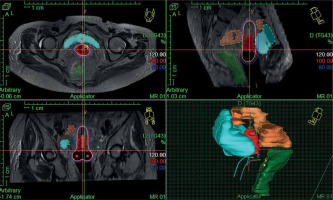

In the first fraction of IGBT, T2-weighted sequences in para-axial, para-sagittal, and para-coronal planes were obtained on 3T MRI (GE Healthcare) with a pelvic coil, which were used for IGBT planning during the first session. Subsequent three BT sessions were done under CT guidance using CT scanner (Siemens Somatom Sensation Open). MRI/CT images were acquired without intravenous contrast at 3 mm slice thickness covering an anatomical region extending from the L4-L5 vertebrae to the ischial tuberosity. Then, the MR/CT images were imported into Oncentra TPS version 4.5.3 (Nucletron, an Elekta company, Elekta AB, Stockholm, Sweden). Delineation of HR-CTV during first fraction was performed according to GEC-ESTRO recommendations [17, 18]. Delineation of HR-CTV was based on MRI information at the time of first fraction supported by clinical examination findings. HR-CTV volume included the entire cervix, gross disease at the time of IGBT, and grey zones on MRI. HR-CTV was delineated on CT images for subsequent fractions (CT1, CT2, CT3) according to Viswanathan et al. guidelines [26]. HR-CTV delineation on CT was based on clinical examination at the time of brachytherapy as well as information from MRI done at the first fraction of IGBT. Volumes and dimensions of HR-CTV were noted at each fraction of IGBT. Prescribed dose was 7 Gy × 4 fractions to HR-CTV (volume-based plan) for all patients (Figure 2), and DVHs for HR-CTV and OARs were evaluated. D90 (minimum dose covering 90% of target volume) of HR-CTV was recorded for all patients. D2cc (minimum doses calculated at the most irradiated 2 cc volumes) of the bladder, rectum, and sigmoid colon were assessed. The total reference air-kerma (TRAK) values and point-A doses for each fraction were also documented. Cumulative doses to HR-CTV and OARs (WP-IMRT and IGBT) were converted to equivalent doses in 2 Gy per fraction (EQD2) using linear-quadratic model (with α/β value of 10 for tumor, and α/β value of 3 for OARs) [27].

EQD2 of WP-IMRT and IGBT were summed up to evaluate the volume-based plan with regards to DVH constraints corresponding to a prescribed EQD2 dose of at least 80 Gy α/β 10 (D98% of WP-IMRT plus D90% of IGBT). For OARs, cumulative total EQD2 dose (D2% of WP-IMRT plus D2cc of IGBT) were aimed to be ≤ 65 Gy α/β 3 for the rectum, ≤ 70 Gy α/β 3 for the sigmoid, and ≤ 80 Gy α/β 3 for the bladder, respectively. IGBT treatment was delivered with iridium-192 source (MicroSelectron HDR, Nucletron, an Elekta company, Elekta AB, Stockholm, Sweden). After completion of the treatment, applicators were removed, and routine antibiotics and symptomatic medications were advised to avoid infections and patients’ discomfort.

Table 3 shows the comparison of HR-CTV doses, dimension, volumes, point-A doses, and TRAK for different fractions of IGBT. The median per fraction doses of IGBT for D2cc bladder, D2cc rectum, and D2cc sigmoid colon were 5.01 Gy (range, 3.5-5.8 Gy), 3.4 Gy (range, 2.2-5.1 Gy), and 3.7 Gy (2.2-5.2 Gy), respectively. The median cumulative doses in terms of EQD2 of IGBT plus WP-IMRT for D90 HR-CTV, D2cc bladder, D2cc rectum, and D2cc sigmoid colon were 87 Gy (range, 81.8-95.8 Gy), 72.95 Gy (range, 65.3-83.2 Gy), 63.1 Gy (range, 57.8-68.8 Gy), and 65.6 Gy (range, 61.2-75.2 Gy), respectively. Cumulative EQD2 of < 85 Gy for D90 HR-CTV, > 80 Gy for the bladder, > 65 Gy for the rectum, and > 70 Gy for the sigmoid were recorded in 3 (12%), 2 (8%), 1 (4%), and 2 (8%) patients, respectively. Cumulative EQD2 to HR-CTV D90 doses in patients with partial responses (n = 7) were > 85 Gy.

IGBT in LACC has shown improvement in dose volume parameters and clinical outcome owing to enhanced HR-CTV and reduced OARs doses [19-23]. In our study, we found similar results as in EMBRACE studies [21], with median EQD2 of D90 HR-CTV, D2cc bladder, D2cc rectum, and D2cc sigmoid colon as 87 Gy (range, 81.8-95.8 Gy), 72.95 Gy (range, 65.3-83.2 Gy), 63.1 Gy (range, 57.8-68.8 Gy), and 65.6 Gy (range, 61.2-75.2 Gy), respectively, which resulted in decent LRC and reduced treatment-related morbidity. The median HR-CTV volumes for the first fraction (MRI), second fraction (CT1), third fraction (CT2), and fourth fraction (CT3) were 21.06 cc (range, 17.2-30.0 cc), 28.4 cc (range, 21.74-34.4 cc), 27.05 cc (range, 22.7-32.5 cc), and 25.6 cc (range, 20.05-31.03 cc), respectively. The HR-CTV volumes in CT-planned fractions were larger as compared with the MRI-planned fractions, and this slight overestimation have been also reported by previous studies [24].